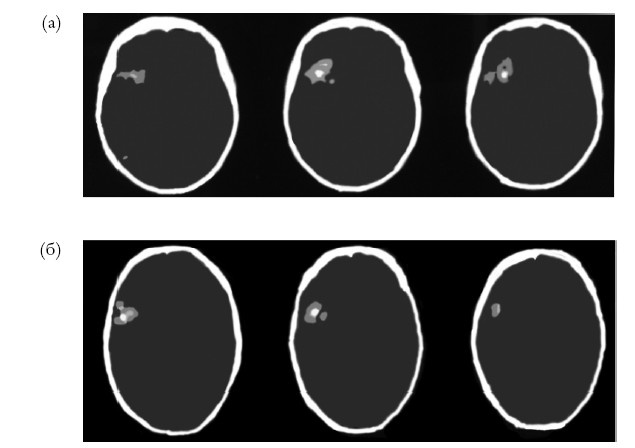

Результаты этого сравнения подтвердили, что правое полушарие особенно активно на ранних стадиях открытия как общего принципа, так и специфических правил Висконсинского теста, в полном соответствии с гипотезой новизны-привычности. Точнее, правые префронтальные области были активными на ранних стадиях «открытий» обоих типов, что опять возвращает нас к лобным долям (рис. 6.2).

Иллюстрация к книге — Креативный мозг. Как рождаются идеи, меняющие мир [i_013.jpg]

Рис. 6.2. Визуализация при помощи функциональной магнитнорезонансной томографии (фМРТ) во время выполнения Висконсинского теста сортировки карточек (WCST). (а) Области, более активные во время выполнения первых трех, чем последних трех категорий. (б) Области, более активные во время выполнения первой половины, чем второй половины каждой категории